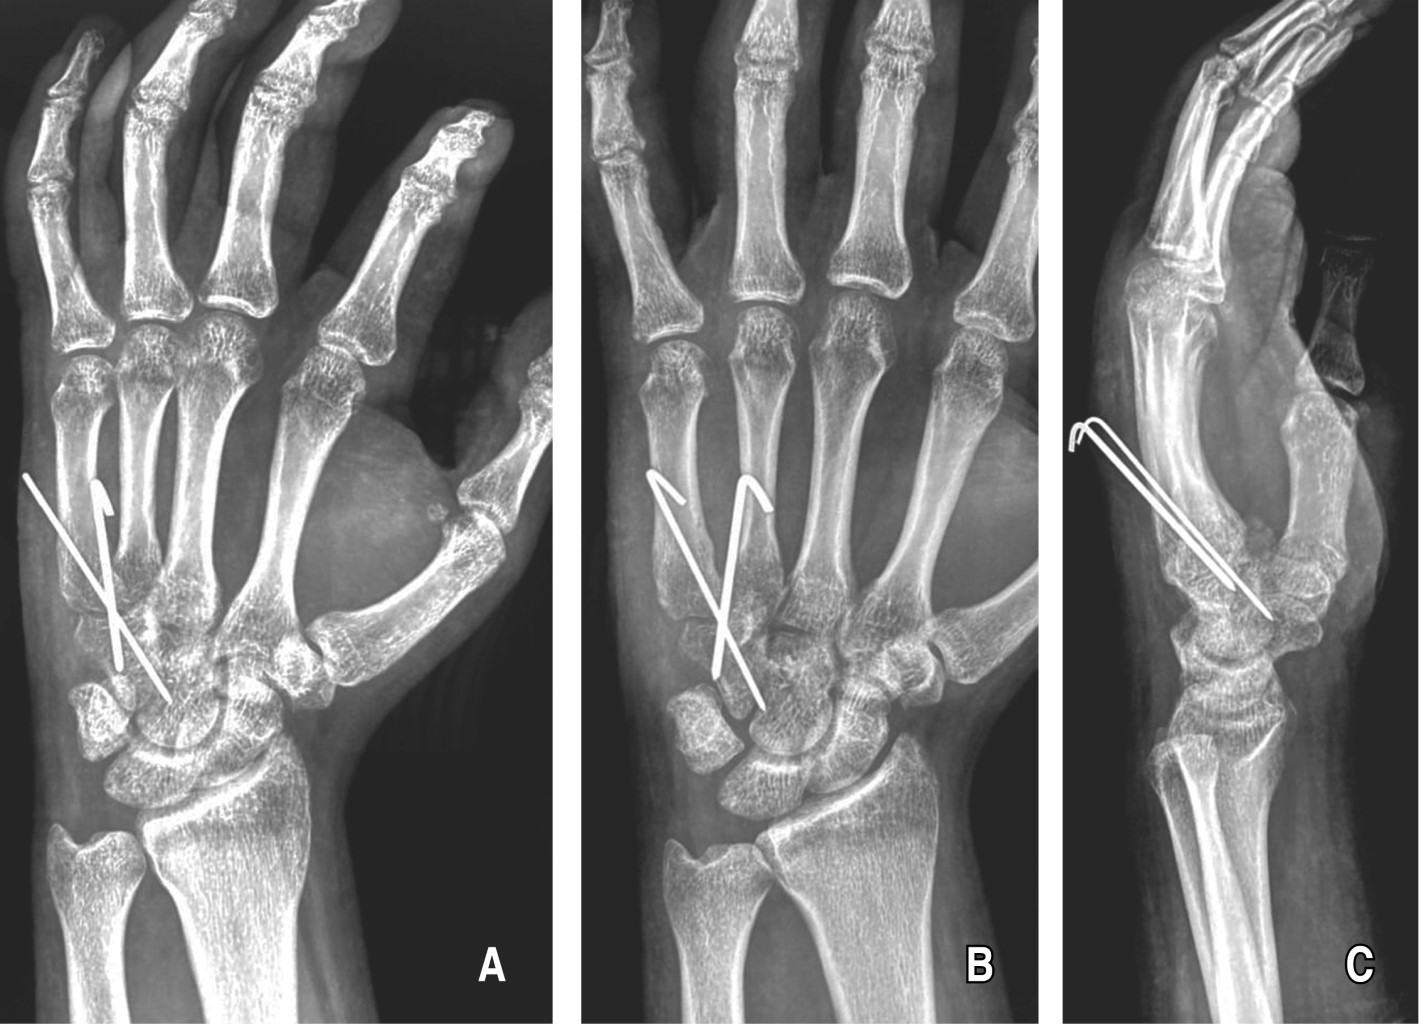

Se corrobora con buena reducción articular del cuarto y quinto dedo de la mano (Figura 3). Se realizó aseo quirúrgico final con solución estéril por barrido y cierre quirúrgico por planos, concluyendo con sutura no absorbible en piel. Se colocó vendaje estéril. Se retiró la isquemia aplicada y se colocó férula antebraquipalmar de muñeca izquierda, concluyendo la cirugía.

Cuenta con radiografía dorsopalmar, oblicua y lateral de muñeca izquierda; se corrobora congruencia articular de la base del cuarto y quinto metacarpiano de la mano izquierda. Presencia de dos clavillos Kirschner de la base del cuarto y quinto metacarpiano al ganchoso, cumpliendo la meta quirúrgica (Figura 4).

Figura 3

Figura 4